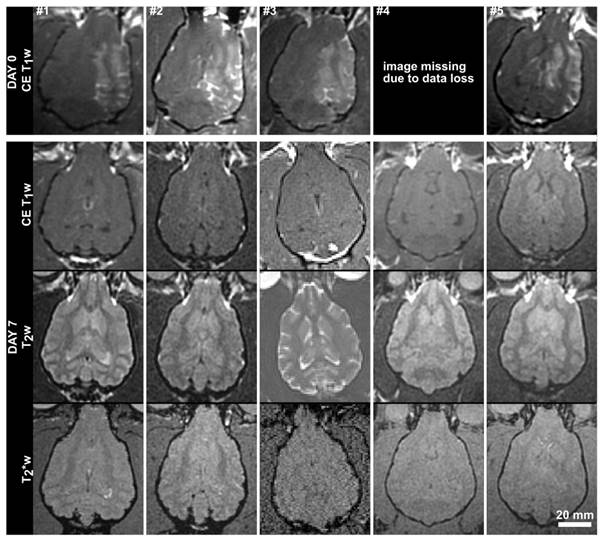

Fig 4

MR (axial) images from the 5 subjects in the acute treatment group acquired immediately post-treatment and at 7 days post-treatment. Contrast-enhanced (CE) T1w images are shown on Day 0, and CE-T1w, T2w and T2* weighted images are shown for Day 7. The Day 0 image for subject #1 has been resliced from an oblique plane. The Day 7 images for subject #3 were acquired using a different MRI scanner (Siemens Prisma). The scale bar is 2 cm.

The MRI parameters used are summarized in Table 1. All treatments were performed under MRI-guidance at 3T (Signa MR750, GE Healthcare, Milwaukee, Wisconsin). Baseline T1 and T2 weighted images were obtained and are shown for group 1 in Fig.3. Contrast-enhanced (CE) T1 weighted imaging (0.1 ml/kg Gadovist) was used to assess the integrity of the BBB post-treatment, and post-treatment T2 and T2* images were used to identify edema or hemorrhage. Follow-up MR imaging was performed one week following the final treatment, using CE-T1, T2 and T2* weighted imaging. The follow-up imaging was performed on the same MRI scanner used during the treatments, except in one case where the system was unavailable and an alternate 3T platform was used (MAGNETOM Prisma, Siemens Healthcare, Erlangen, Germany).

To compare, the average thickness and density of the supraorbital region of 8 ex vivo human skulls (4 skull caps and 4 full skulls) in our laboratory was extracted from existing CT data. The human skulls were found to be approximately twice as thick (6.4 ± 1.8 mm, maximum 20.3 mm) and were similar but not quite as dense (1900 ± 373 kg/m3, maximum 2975 kg/m3) as the dog skulls. The brain cavities of the 4 full human skulls were 108.4 ± 4.2 mm deep, 137.2 ± 9.9 mm wide and 162.3 ± 5.2 mm long. Despite the bone morphology, the permeability of the BBB was successfully increased unilaterally using transcranial ultrasound (Fig.4). A mean enhancement of 19 ± 11% was observed across all treatments relative to the untreated hemisphere. Heterogeneous patterns of enhancement were observed in all animals. Enhancement was not seen in the white matter tracts, which is consistent with investigations of BBB opening in primates [12] and can be attributed to the fact that white matter is poorly vascularized resulting in limited signal from the extravasated contrast agent. The post-treatment images for animal #4 are missing due to a data loss, but the degree of enhancement and the heterogeneity of the enhancement were in keeping with the other four animals in the single treatment group. The mean intensity across the entire hemisphere relative to the control hemisphere is shown for each treatment and follow-up in Fig.5. These are expressed as (1-mean_intensitytreated/mean_intensityuntreated)*100%, and thus negative values can occur when the mean intensity of the treated side is lower than the control side. Also shown are the mean intensity in an unsonicated region (usually in the olfactory bulb or cerebellum) of the treated hemisphere relative to the same region on the treated side. This control region is included because in some cases there were substantial differences in the intensity of the MR images resulting from the positioning of the surface coil. For example, the coil placement during the follow-up imaging of animal #6 resulted in an intensity gradient left to right across the brain. Examining only the treated vs. untreated intensities makes it appear that there is enhancement in the treated region. Examining the unsonicated control region, it can be seen that the higher intensity in the left hemisphere is unrelated to the treatment region. The heterogeneity of the BBB opening is reflected by the large standard deviations in the treated hemispheres.